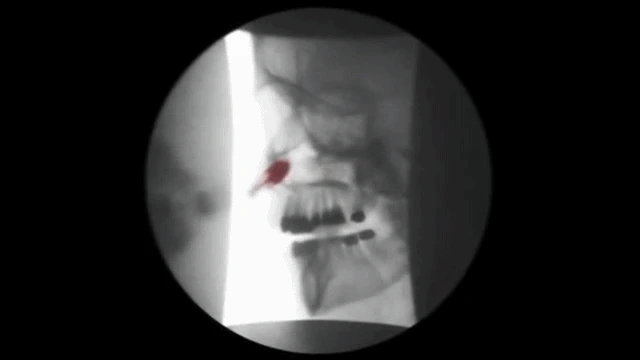

턱관절의 변형은 FCST라는 치료법으로 교정치료 합니다.

상악의 문제는 CFRT라는 두개안면골재배열술이 중심이 되지요.